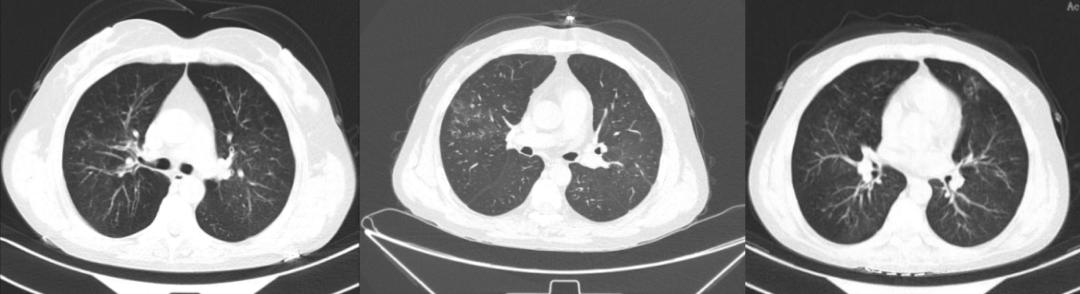

经讨论,我们可先选择无创,有创检查尽可能床旁进行。完善血常规,ANCA抗体、胸部CT、血清IgG4、支气管镜及组织病理等检查,且病理一定要做IgG4阳性细胞计数,肺功能检查也需要复查。但患者呼吸衰竭明显,无法外出配合肺功能检查。我们先完善了无创的检查,血常规检查情况为:WBC 14.2×10^9/L,Hb 149g/L,PLT 235×10^9/L,NE%72.2%,EOS% 6.0%;电解质、血糖、血脂、肝肾功能、血凝六项及传染病无异常风湿免疫抗体:ANA、抗ENA酶谱、ANCA四项阴性;免疫球蛋白IgE:689.80IU/m;血清IgG4浓度4.18g/L。患者的嗜酸性粒细胞升高、免疫球蛋白IgE升高、IgG4浓度升高,支持IgG4相关疾病。胸部CT显示:双肺支气管纹理粗乱,通气不均匀,具备可见马赛克灌注(图4),不支持肺部结节病引起的呼吸困难。

图4:胸部CT